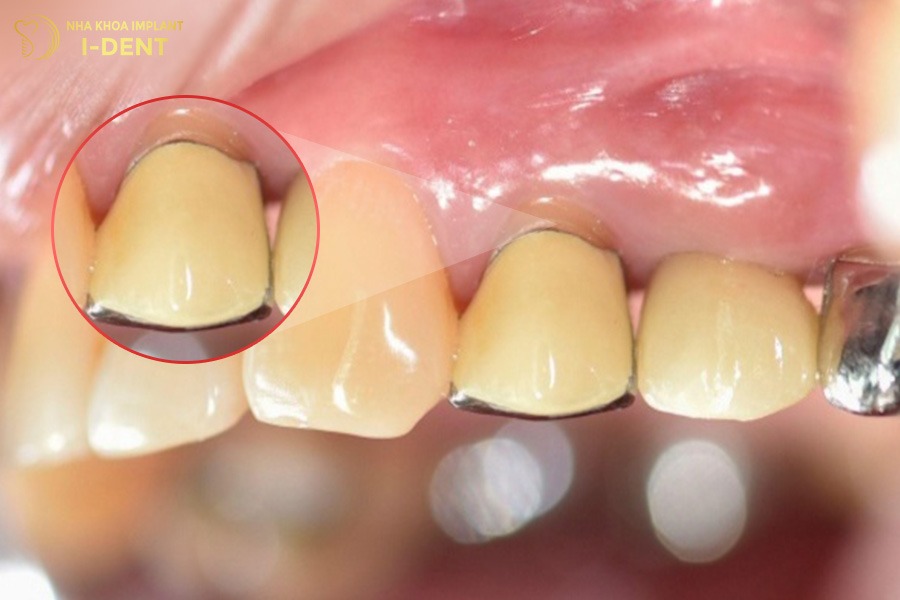

1.3. Xuất hiện vệt đen mờ quanh chân răng

Tình trạng xuất hiện vệt đen mờ quanh chân răng là dấu hiệu răng sứ bị hở thường gặp đối với những người bọc răng sứ kim loại. Khi răng sứ kim loại không ôm khít với viền nướu sẽ dẫn đến hiện tượng oxy hóa phần kim loại bên trong, gây xỉn màu tại viền nướu.

Với dấu hiệu này, bạn có thể quan sát được bằng cách nhìn kỹ vùng chân răng sứ thấy có những vệt đen hoặc sẫm màu.

Bọc răng sứ kim loại bị hở dẫn đến răng sứ bị oxy hóa làm xuất hiện vệt đen mờ quanh chân răng sứ.